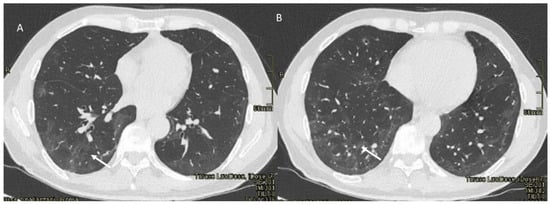

Pulmonary Lymphangitis Carcinomatosa

| Type of Pneumonia | Lung Involvement | CT-Patter |

|---|---|---|

| COVID-19 Pneumonia | Diffuse (related to the phase of disease) | ground-glass opacity, crazy-paving pattern, consolidative opacities, interlobular septal thickening (according to the phase of disease) |

| RRR-Related Vaccine | Target Area | Consolidative opacities |

| Pulmonary lymphangitis carcinomatosa | Diffuse (related to the phase of disease) | Irregularly interlobular septal thickening, smooth (early stage), or nodular thickening (late development), ground-glass opacity, pleural effusions. |

| ICI-Related Pneumonitis | Diffuse (related to the phase of disease) | ground-glass and reticular opacities, consolidative opacities, interlobular septal thickening, “crazy-paving” pattern |